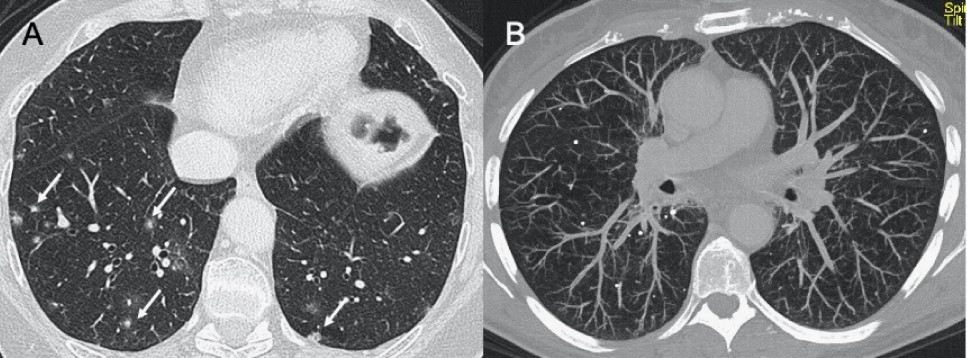

?Sars-CoV-2(即新型冠狀病毒)

● CXR:肺胸膜下實變、磨玻璃影、結節和網狀結節陰影,表現為間質性肺炎伴彌漫性肺泡損傷(圖1)。

● CT:早期主要為外周、雙側磨玻璃影(ground-glass opacities,GGO),伴實變、小葉間隔和小葉內間隔增厚,形成“鋪路石征”模式??諝庵夤苷?、血管擴大、暈輪征和反暈征也有報告(圖2)。

圖1 新冠肺炎(COVID-19)的CXR。3例仰臥位CXR顯示胸膜下實變(箭頭),圖(A,B)顯示雙側受累,(C)主要為右肺受累

圖2 COVID-19的HRCT。急性期,雙肺(A)彌漫性GGO,小葉周圍型(B)。圖(C,D)顯示2例亞急性間質性肺炎,GGO減少,存在胸膜下局灶性實變和小葉間/小葉內間質增厚。